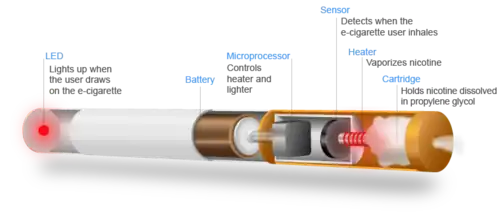

Mechanism

Vaping refers to the practice of inhaling an aerosol from an electronic cigarette device,[4] which works by heating a liquid that can contain various substances, including nicotine, tetrahydrocannabinol (THC), flavoring, and additives (e.g. glycerin (sold as vegetable glycerine (VG)), propylene glycol (PG)).[8] The long-term health impacts of vaping are unknown.[4]